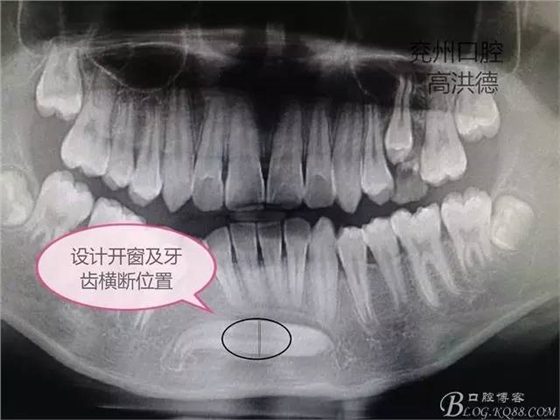

常規(guī)查體,嚴(yán)格控制手術(shù)的禁忌癥和適應(yīng)癥,術(shù)前談話,簽手術(shù)協(xié)議。

手術(shù)設(shè)計(jì);下頜前庭溝做約3CM的切口,分離粘骨膜,高速手機(jī)去骨,暴露牙齒中端,截?cái)嘌例X分別取出,牙冠和牙根。